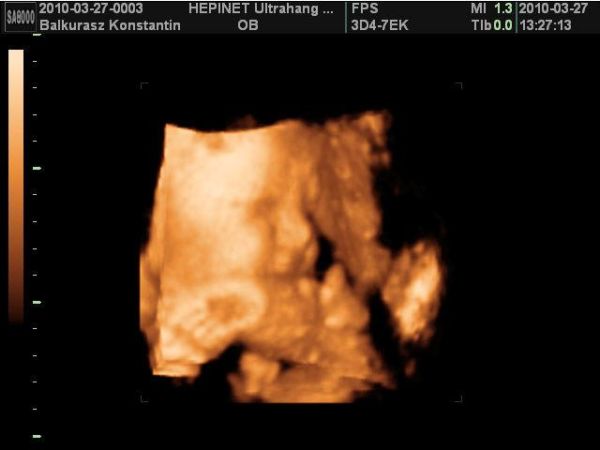

A legutóbbi uh-n 1985 gramm volt a picur. De nagyon bújós. :D :D Azt mondták lehet 4 kg-os is mire megszületik.

Küldök én is fótót a legutóbbi uh-ról. Csak a kezét nagyon oda tette az arca elé. Így a száját nem lehet látni.